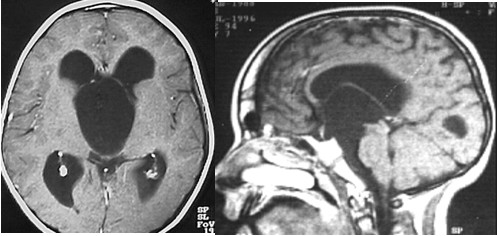

Przedstawiony na rycinie obraz badania MRI uwidacznia patologię wywołującą wodogłowie o typie obturacyjnym - z charakterystycznym obrazem poszerzonego układu komorowego o wyglądzie tzw. „głowy Myszki Miki”.

Zaproponuj optymalny sposób postępowania.

1) implantacja zastawki komorowo-otrzewnowej;

2) operacja otwarta z dojściem transcallosalnym usunięcie ścian torbieli;

3) endoskopowe połączenie światła torbieli z układem komorowym mózgu

w obrębie otworu Monro;

4) endoskopowa akweduktoplastyka;

5) endoskopowe połączenie jamy torbieli ze zbiornikiem przedmostowym;

6) przebicie blaszki granicznej tzw. operacja Scarffa-Stookeya.